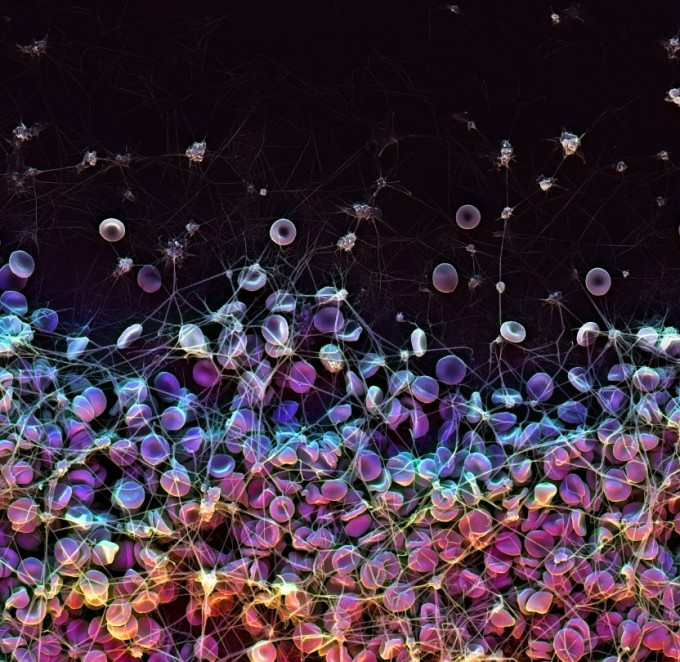

Bioinspired coating for medical devices avoids clotting and suppresses bacterial infection

Repels blood and bacteria, including biofilms